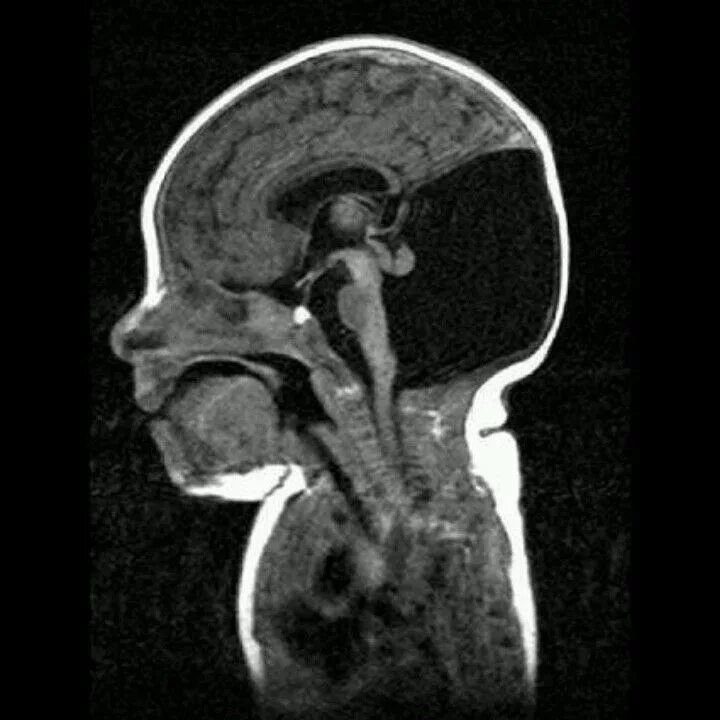

Денди уокера мрт